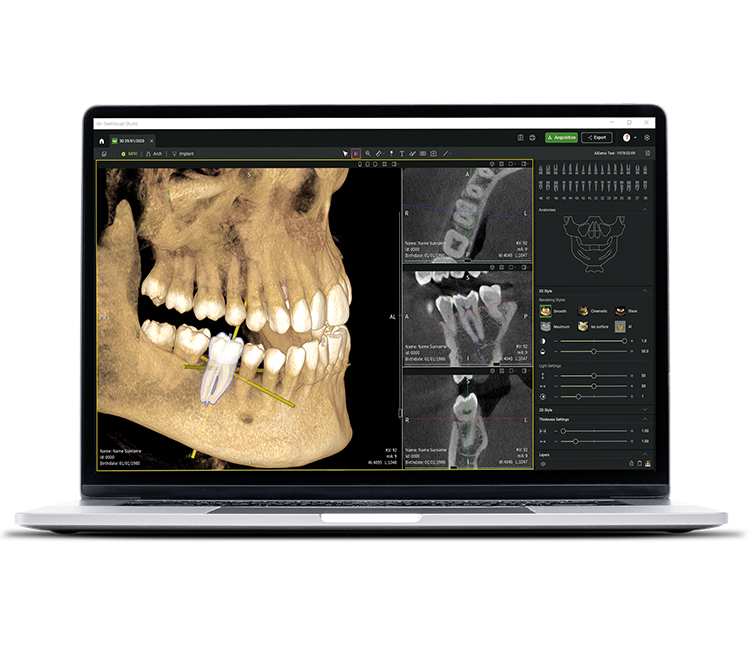

• Seethrough Studio

See tomorrow. See a new level.

En plus des technologies matérielles sophistiquées, le logiciel Seethrough Studio révolutionnaire est le facteur déterminant pour assurer le niveau de qualité élevé de l’ensemble de la gamme de solutions d’imagerie de W&H :avec des fonctions utiles et des algorithmes avancés, Seethrough Studio est une solution intégrale qui élève l’imagerie et les flux de travail en odontologie numérique à un niveau supérieur.

Intégration impeccable

Seethrough Studio s'intègre facilement à votre système de gestion des patients. Vous pouvez lancer le logiciel directement depuis le PMS sans avoir à saisir à nouveau les données du patient.

Sélection libre du FOV sur l’image du dispositif d’exploration

Pour une image correcte dès le premier cliché : sélectionnez le FOV nécessaire dans l’aperçu fourni par le dispositif d’exploration et ajustez librement la zone concernée. Cela permet de positionner le

FOV avec précision et d’éviter de réaliser un nouveau cliché.

Correction des mouvements et de la position du patient

L’algorithme perfectionné de

correction des mouvements fait passer la qualité d’image au niveau supérieur, à la fois pour l’imagerie 3D et pour l’imagerie 2D. Les images 2D sont encore améliorées par un système de mise au point automatique à 21 couches, parfaitement intégré dans une correction de positionnement.

Suppression des artefacts métalliques (MAR)

Rétablit l’intégrité de l’image en retirant les artefacts métalliques et permet d’examiner des images avec ou sans MAR, pour une visualisation flexible et un diagnostic plus précis.

Des images nettes, détaillées et sans distorsion

Grâce aux algorithmes avancés de Seethrough Studio.

Outil de planification implantaire intégré

En plus d’une qualité d’image exceptionnelle et d’une utilisation intuitive, Seethrough Studio offre de

nombreuses fonctions utiles, comme un outil de planification d’implants intégré par défaut, pour simplifier la visualisation et la préparation du traitement.

Fonctions assistées par l'IA

Seethrough Studio a recours à différents outils d’IA pour améliorer encore davantage l’imagerie, par

exemple l’orientation des volumes 3D, la segmentation dentaire, le tracé des arcades, la détection automatique du canal mandibulaire

et une assistance précieuse pour la suggestion de pathologies.